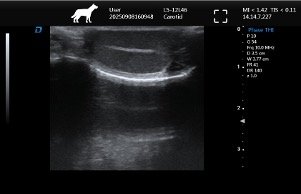

| Imaging Quality | Clear 2D, stable grayscale, optional Color Doppler for abdominal, cardiac, reproductive exams | Ensure system covers most frequent clinical exams |

| Probe Versatility | Supports convex, linear, micro-convex probes | Match probes to clinic’s routine exams |

→ Step 2: Match Probe Options to Applications – Ensure the system supports required probes with appropriate frequency ranges for small animal imaging.